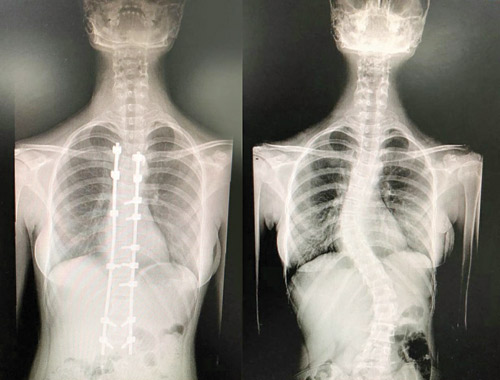

من جانبه قال د. واصف السباعي استشاري جراحة العظام والعمود الفقري ورئيس الفريق الطبي المعالج للحالة الثانية أن الطفلة جاءت إلى المستشفى وهي تشتكي من انحناء للعمود الفقري وتحدب وآلام في الظهر، إضافة إلى صعوبة في ممارسة الحياة الطبيعية، وفور وصولها إلى المستشفى أخُضعت للتحاليل والفحوصات الطبية الدقيقة، التي أكدت إصابتها بحالة انحراف واعوجاج متزايد في العمود الفقري، فتم دراسة الحالة على ضوء نتائج الفحوصات والتحاليل وتبين أهمية التدخل الجراحي لعلاج العيوب والحد من المضاعفات، وبعد اتخاذ التدابير اللازمة، أجريت لها عملية جراحية تم فيها تقويم العمود الفقري وتثبيت ودمج الفقرات، واستخدمت في العملية مجموعة من أحدث الأجهزة الطبية التي ساهمت مع الكوادر الطبية عالية الكفاءة والتأهيل بمستشفى د.سليمان الحبيب بالعليا في إنجاح العملية.